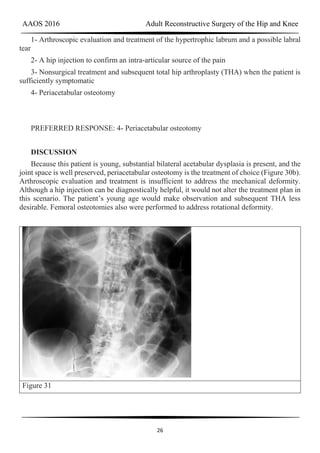

DISCUSSION

Because this patient is young, substantial bilateral acetabular dysplasia is present, and the

joint space is well preserved, periacetabular osteotomy is the treatment of choice (Figure 30b).

Arthroscopic evaluation and treatment is insufficient to address the mechanical deformity.

Although a hip injection can be diagnostically helpful, it would not alter the treatment plan in

this scenario. The patient’s young age would make observation and subsequent THA less

desirable. Femoral osteotomies also were performed to address rotational deformity.

Figure 31